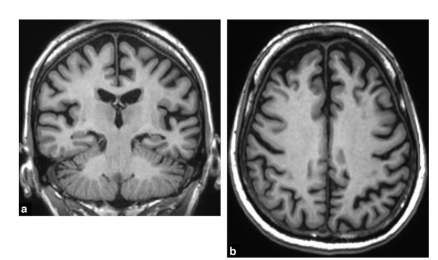

Alzheimers

Large amount of brain degeneration

Enlargement of subarachnoid space, enlarged venticles